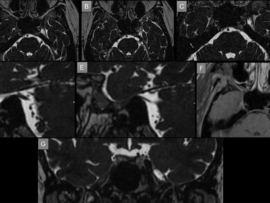

45 YEAR OLD MALE, Presenting compaints: Patient presented with lower back pain since 5 years; right leg numbness and tingling since 6 months and acute onset urinary incontinence